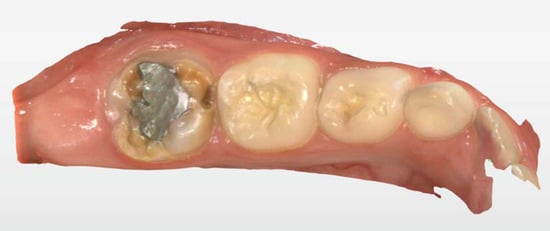

2.2. Clinical Case